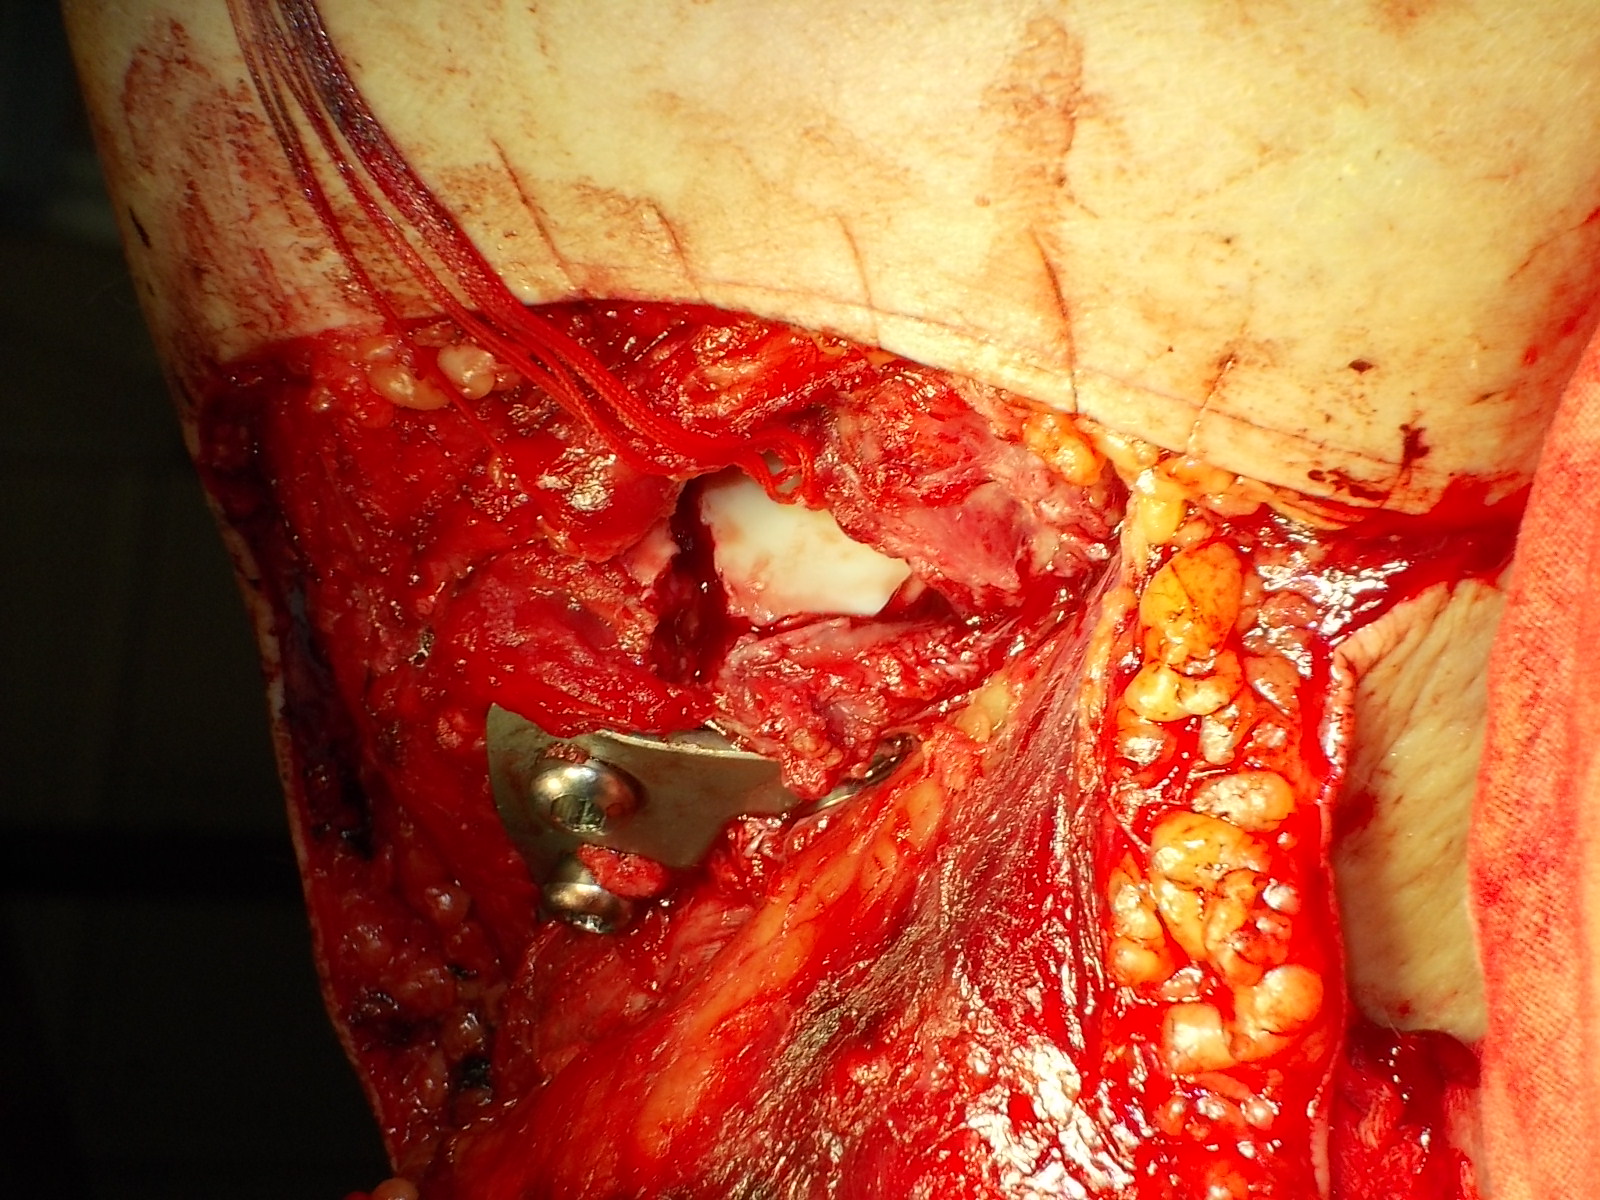

Операция - открытая репозиция, остеосинтез большеберцовой кости опорной пластиной с костной ксенопластикой маетриалом "Остеоматрикс". На контрольных снимках в три и шесть месяцев имеется консолидация перелома, миграции фиксатора нет, имеется остеоинтеграция ксенопластического материала. Функция коленного сустава полная.